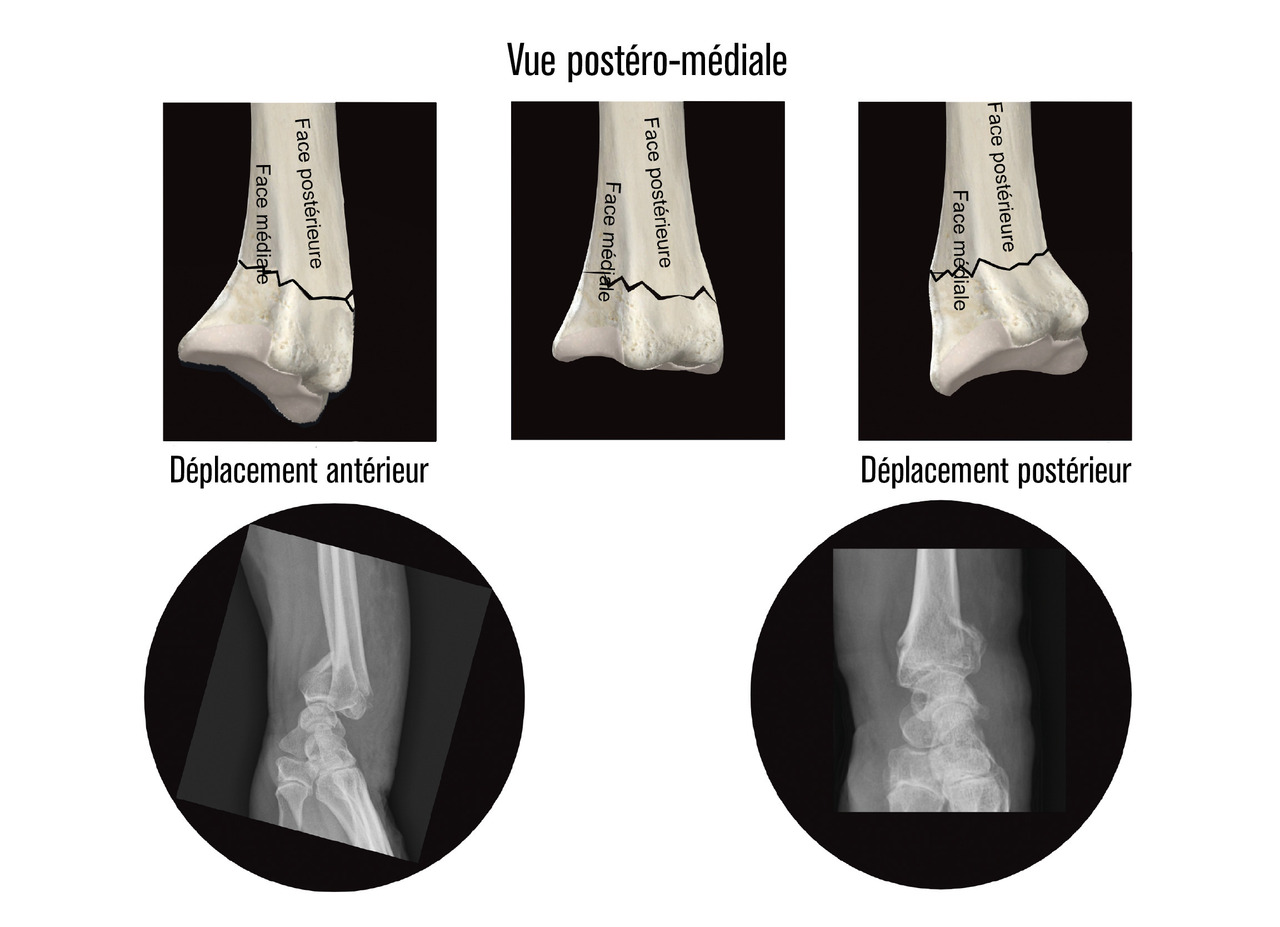

Au niveau métaphysaire le déplacement peut être postérieur ou antérieur (fig. 6). En ce qui concerne le déplacement postérieur, il est important de se souvenir que la surface articulaire regarde vers l’avant. En d’autres termes, dès que cela n’est plus le cas, même si la surface articulaire n’est pas orientée vers l’arrière, il s’agit d’un déplacement postérieur. Classiquement, le déplacement postérieur est lié à un mécanisme dit en compression-­extension, c’est-à-dire une chute sur la main, le poignet étant en extension (fig. 7). Le déplacement est dit antérieur s’il y a une exagération de l’orientation antérieure de l’épiphyse radiale. Ce déplacement est classiquement lié à un mécanisme dit en compression-flexion, c’est-à-dire une chute sur la main, le poignet étant en flexion (fig. 7). La plupart du temps, ce déplacement postérieur ou antérieur s’accompagne également d’un déplacement externe, avec un tassement au niveau de la corticale latérale (fig. 8). Outre le déplacement antérieur, postérieur ou latéral, il est très important d’analyser au niveau du foyer de fracture métaphysaire l’importance de la comminution qui peut être uniquement postérieure, ou antérieure, ou circonférentielle, ce qui conditionne la stabilité de la fracture et oriente vers le type d’ostéosynthèse à réaliser.